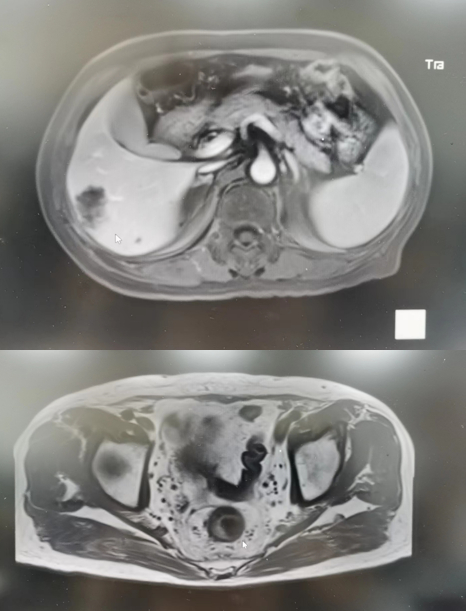

腹部MRI(2021年05月05日):1.肝右后叶下段(VI段)占位性病变,考虑转移(5×3.7cm)(图2)。

图2 2021年05月05日上腹部MRI